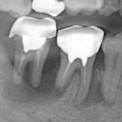

症例1

長期に渡る清掃不良のため、根元に真っ黒な歯石が厚く付着しています。左下 1 番(向かって右の歯)は完全に位置がずれ浮いてしまっています。

左の写真のレントゲン像です。右下 2 番から左下 2 番は抜歯となりました。右下 3 、 4 と左下 3 、 4 は辛うじて保存可能でした。